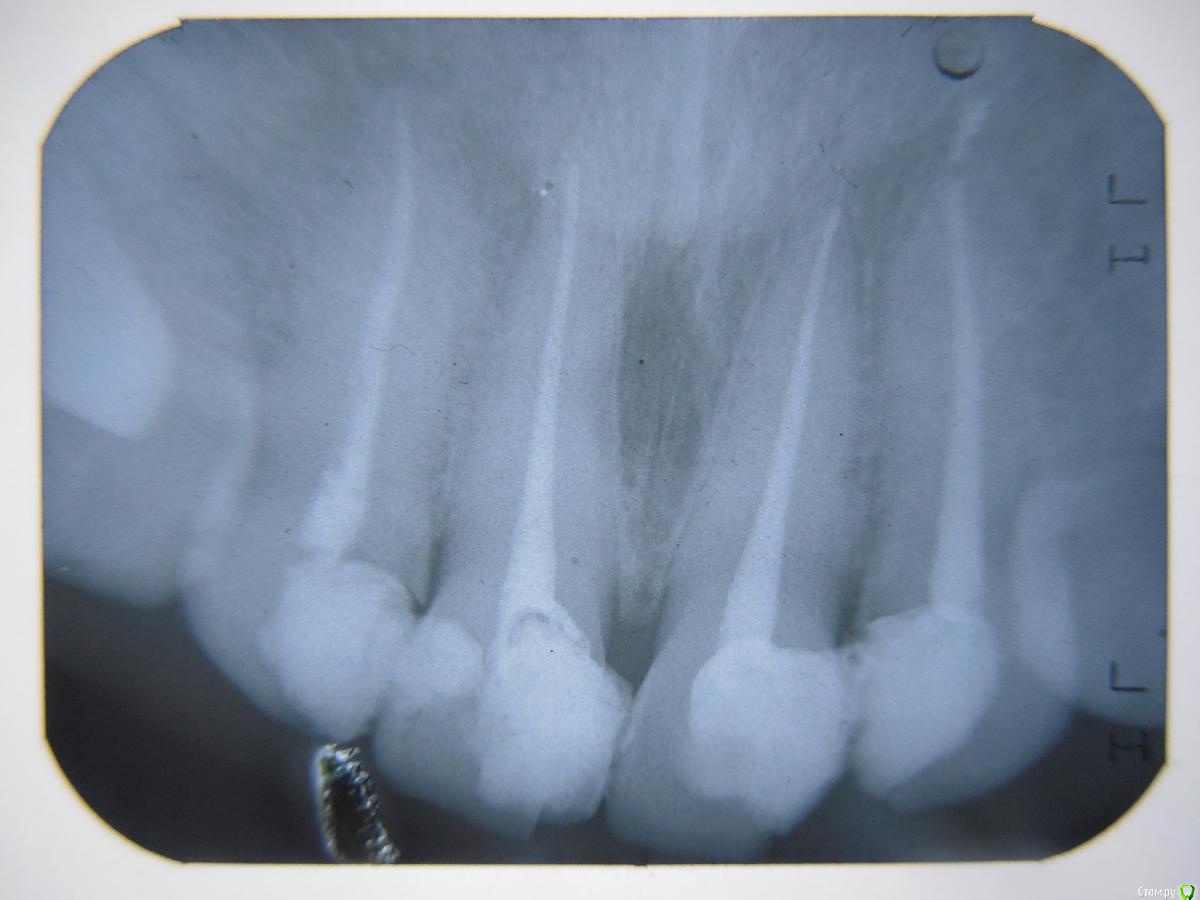

Andrian Опубликовано 30 июля, 2019 Автор Поделиться Опубликовано 30 июля, 2019 (изменено) Причинная единичка на снимке справа. Добавлю что в глубине десны в "болевой" точке прощупывается небольшая шишка. все четыре зуба свежедепульпированы. Изменено 30 июля, 2019 пользователем Andrian Ссылка на комментарий

DmitrySH Опубликовано 30 июля, 2019 Поделиться Опубликовано 30 июля, 2019 На снимке все нормально выглядит 1 Ссылка на комментарий

St. Опубликовано 30 июля, 2019 Поделиться Опубликовано 30 июля, 2019 Причинная единичка на снимке справа. Добавлю что в глубине десны в "болевой" точке прощупывается небольшая шишка. все четыре зуба свежедепульпированы.по снимку все хорошо. Подождите, чувствительность и дискомфорт после манипуляций могут быть даже до 2 недель иногда, главное чтоб постепенно становилось лучше 1 Ссылка на комментарий

Andrian Опубликовано 31 июля, 2019 Автор Поделиться Опубликовано 31 июля, 2019 Спасибо. Будем ждатб. А над вторым зубом это что? Не пломбировочный материал? Может на него такая реакция? 1 Ссылка на комментарий

St. Опубликовано 31 июля, 2019 Поделиться Опубликовано 31 июля, 2019 Над 2 есть немного материала за пределами зуба, это не страшно и практически ни на что не влияет 2 Ссылка на комментарий

red_butler Опубликовано 31 июля, 2019 Поделиться Опубликовано 31 июля, 2019 + 1, выведенный материал роли не играет, ряд западных стандартов лечения даже обязывает так делать 1 Ссылка на комментарий